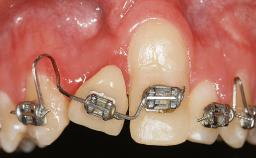

A 30-year-old woman was referred by her general dentist for evaluation of an esthetic complication related to previous implant treatment for congenitally missing maxillary lateral incisors. The patient’s chief complaint was the inadequate esthetic appearance of her smile. The case demonstrates the use of a combined approach to achieve optimal results. Two different flap designs - a tunnel technique and a coronally advanced flap - are employed based on the surgical objectives for the affected site.

Soft Tissue Grafting Yes

Surgical SAC classification

SAC Level Advanced